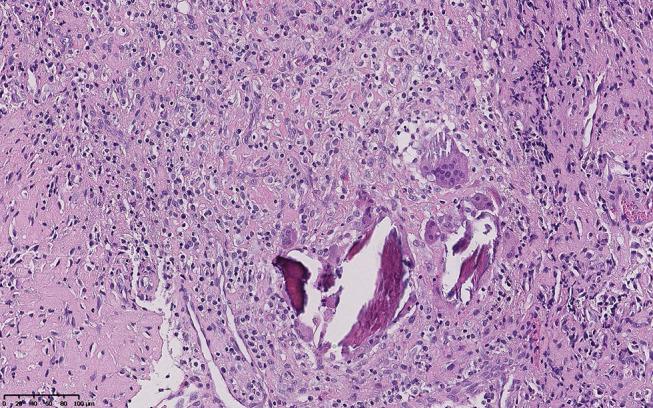

() is a causative pathogen of some rare diseases such as primary atrophic rhinitis and ozena. Here, we describe one case of a potentially lethal kind of infection in which multiple organs were implicated. A 40-year-old diabetic male patient presented to our hospital due to fever with right anterior chest mass and neck and shoulder pain for half a month. Based on all examination results, he was diagnosed with sepsis, bilateral pulmonary/right chest wall/liver abscesses and 5th cervical vertebra bone destruction with prevertebral abscesses, all related with infection. During the first time of admission, he was treated with antimicrobials without operations. Twelve days after his first discharge, fever and pain occurred again, the patient was treated with antimicrobials, operations (anterior debridement, spinal canal decompression, iliac bone graft fusion and internal fixation) and rehabilitation at second admission. The patient recovered well and was discharged from hospital. This case report demonstrates that can trigger a wide range invasive infections. Particularly, 5th cervical vertebra bone destruction was first reported as a clinical manifestation of infection in our patient.

()是一些罕见疾病如原发性萎缩性鼻炎和臭鼻症的致病病原体。在此,我们描述一例涉及多个器官的潜在致命性感染病例。一名40岁的糖尿病男性患者因发热伴右前胸肿块以及颈部和肩部疼痛半个月前来我院就诊。根据所有检查结果,他被诊断为脓毒症、双侧肺/右胸壁/肝脓肿以及第5颈椎骨质破坏伴椎前脓肿,所有这些均与()感染有关。首次入院时,他接受了抗菌药物治疗,未进行手术。首次出院12天后,发热和疼痛再次出现,患者在第二次入院时接受了抗菌药物治疗、手术(前路清创、椎管减压、髂骨植骨融合及内固定)和康复治疗。患者恢复良好并出院。该病例报告表明()可引发广泛的侵袭性感染。特别是,第5颈椎骨质破坏作为()感染的临床表现首次在我们的患者中被报道。